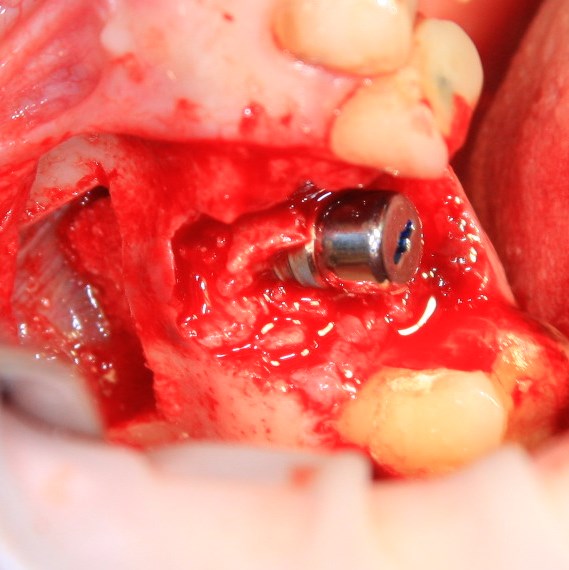

Немедленная имплантация — оптимальное решение в любой клинической ситуации